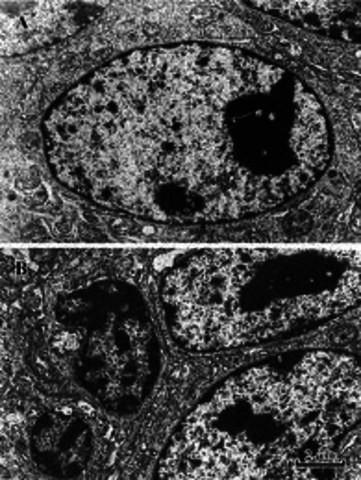

• Robert Brown the cell nucleus in cell of the orchis

Robert Brown the cell nucleus in cell of the orchis

Wouldn't be able to examine cell nucleus